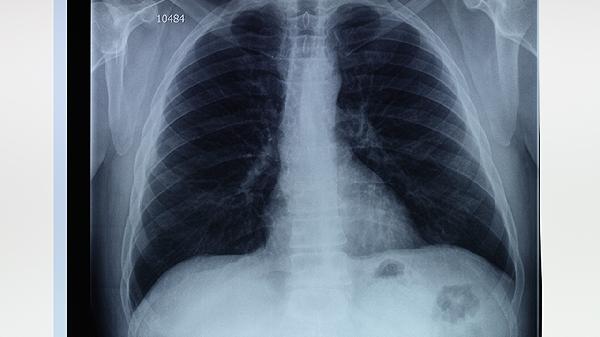

肺大泡可能由慢性阻塞性肺疾病、肺部感染、遗传性α-1抗胰蛋白酶缺乏、长期吸烟或外伤等因素引起,通常表现为呼吸困难、咳嗽、胸痛等症状。肺大泡可通过胸部CT检查确诊,并根据病情选择保守观察、药物治疗或手术切除。